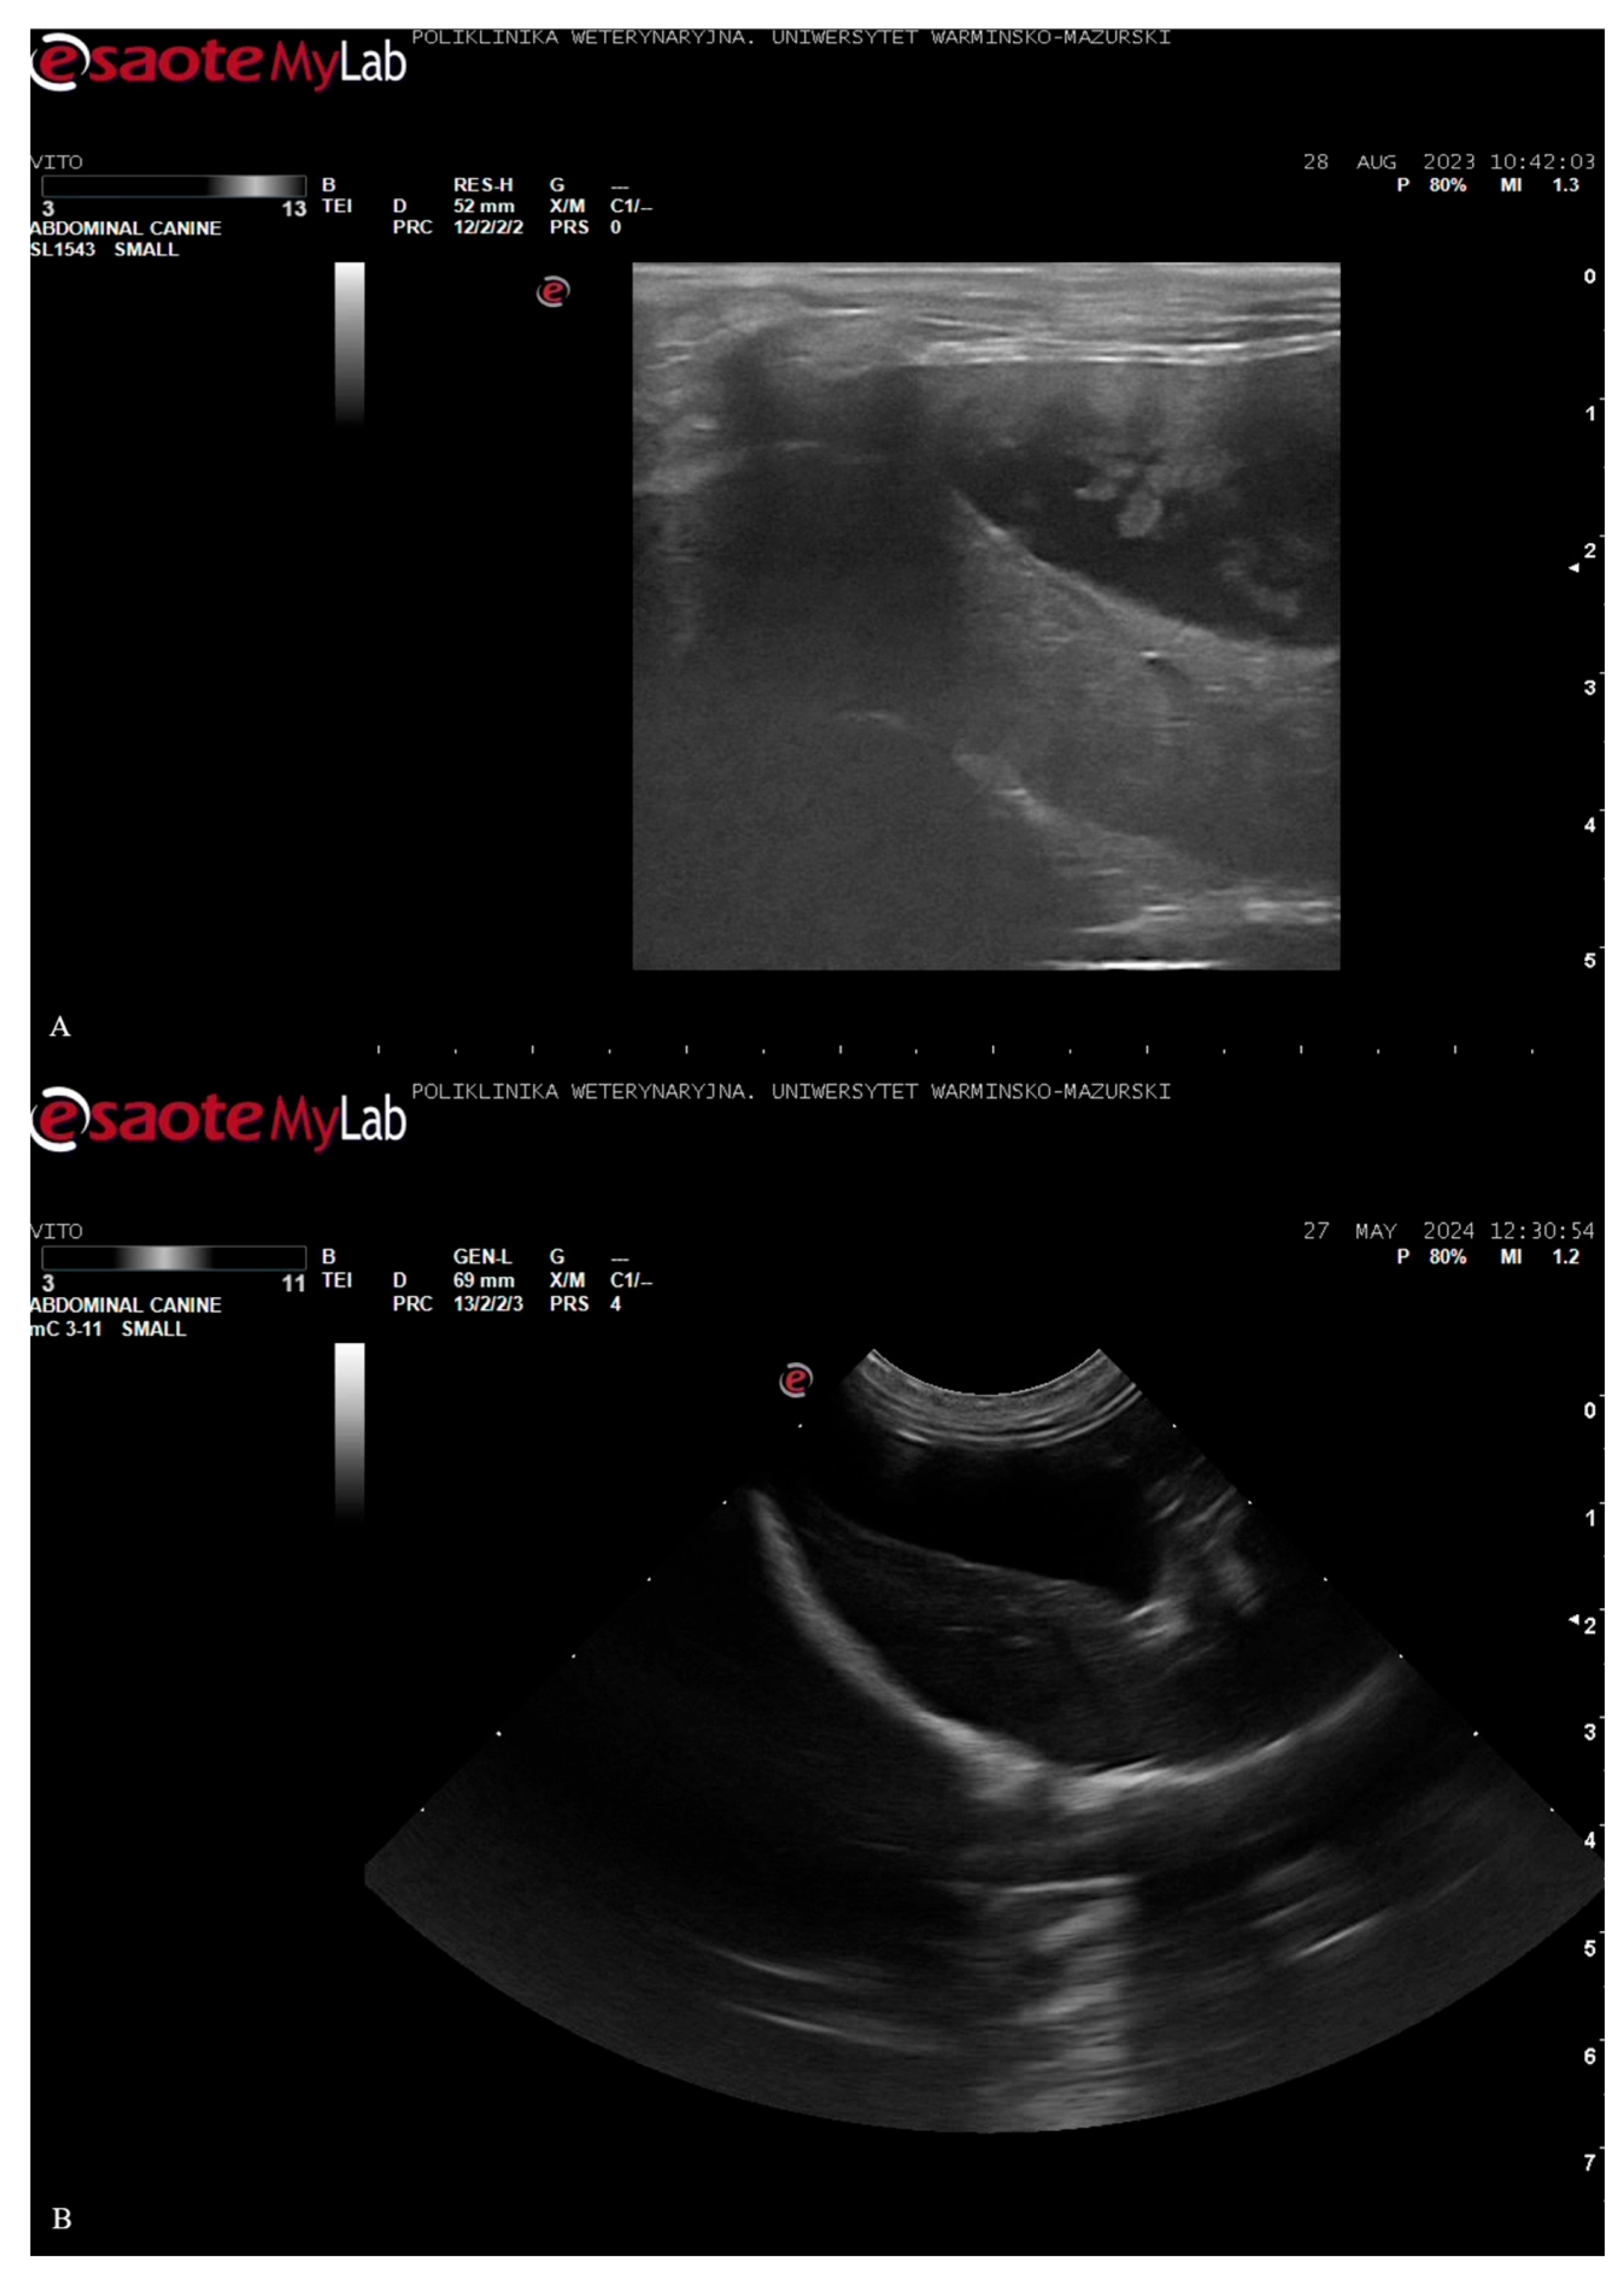

A recheck abdominal ultrasound was performed approximately one week after hospital discharge. Gallbladder sludge reappeared after nearly two years on the T. molitor diet. The above could be attributed to multiple factors, with the recent anorexia and rapid dietary changes as potential contributors. The prescription GI diet, while low in fat, was moderate in fiber and contained ingredients that might have affected bile composition or gallbladder motility. In early August 2023, ursodeoxycholic acid was re-started to help dissolve the sludge. However, the treatment was discontinued by the owner due to difficulties with oral administration. Appetite issues persisted in the following three weeks, and the owner decided to switch back to the T. molitor-based diet (given the dog’s previous positive response and willingness to eat it). The dog’s food intake improved immediately. One month later, a follow-up ultrasound (after around 3–4 weeks on the T. molitor diet) revealed that the sludge had once again cleared (anechoic, normal bile). In October 2023, a repeat ultrasound confirmed that the gallbladder was clear. This timeline suggests that the T. molitor diet might have played a role in maintaining gallbladder health because sludge appeared during the dietary break and was eliminated once the dog had resumed the diet. The patient remained on the T. molitor-based diet, and its condition was assessed as stable in late 2023. Ultrasound images are presented in Figure 1.

Figure 1. Comparative ultrasound images of the gallbladder. A) echogenic bile with sludge accumulation (28 August 2023, after the poisoning incident and several weeks after the discontinuation of the insect-based diet); B) anechoic (black) gallbladder lumen and sludge clearing (27 May 2024, after prolonged adherence to the insect-based diet). The correlation between diet and gallbladder appearance as well as clinical data suggest that the mealworm-based diet not only helped manage the dog’s intestinal disease, but may have also contributed to improved biliary function.